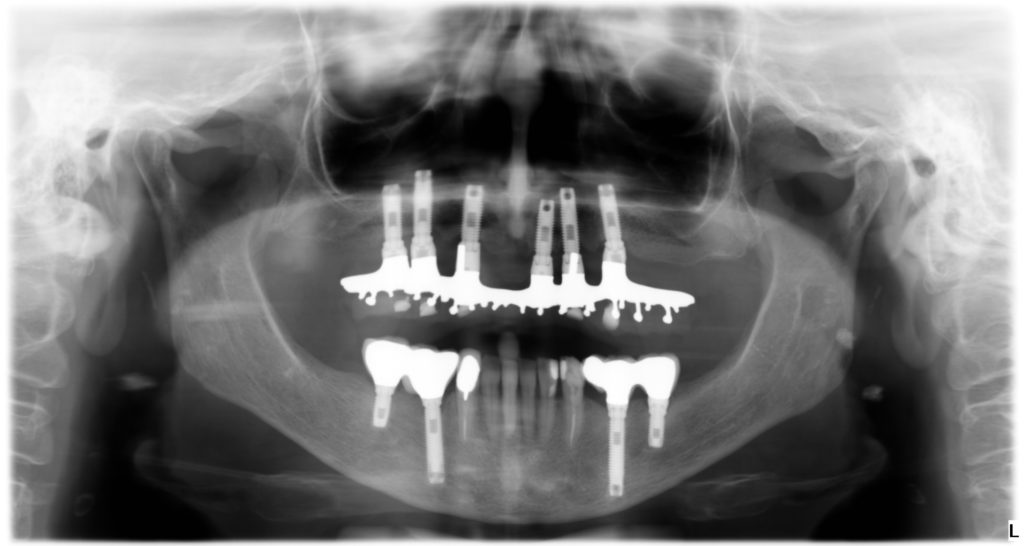

En Martínez-Barona Clínica Dental valoramos mucho explicar a nuestros pacientes los tratamientos que vamos a llevar a cabo y la importancia de la planificación en el tratamiento con implantes. Cuando un paciente necesita rehabilitar piezas dentales que ha perdido por diferentes motivos, ya sea por caries, enfermedad periodontal o traumatismos, necesitará reemplazarlas con implantes. Antes de empezar con [...]